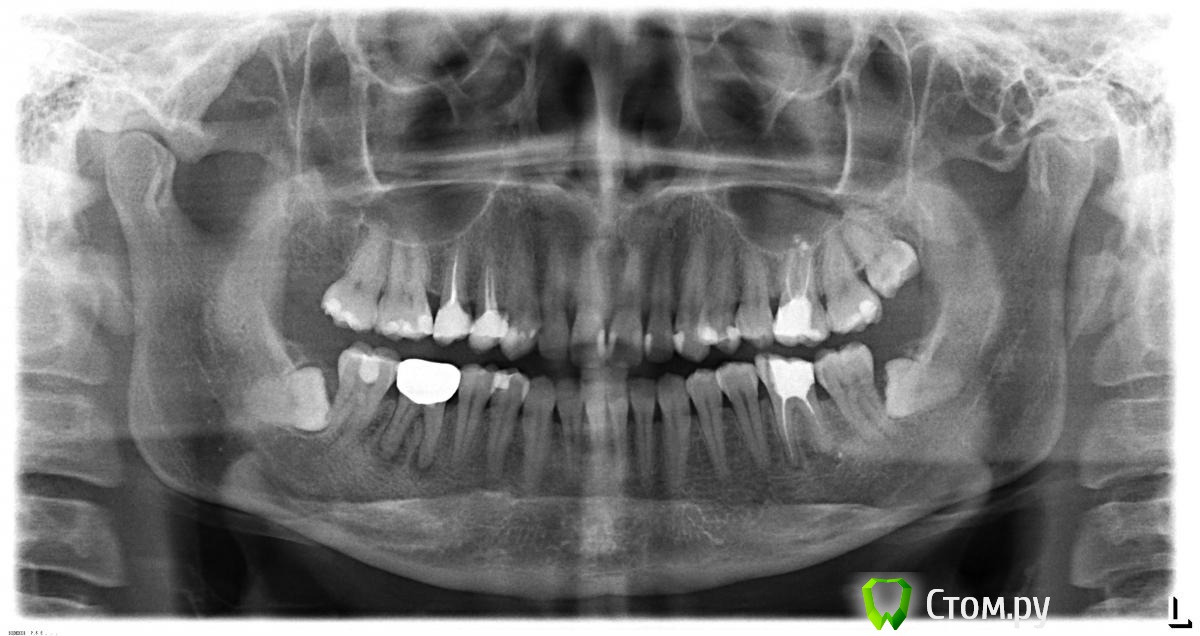

Yana5 Опубликовано 4 января, 2014 Поделиться Опубликовано 4 января, 2014 Здравствуйте! 2) Посоветуйте, пожалуйста, что можно сделать с нижними 6- ками в моем случае? Под коронкой на правой 6-ке началось воспаление, коронку сняли, врач почистил каналы, сейчас она выглядит так: Мне бы хотелось поставить туда коронку, как вы считаете, это возможно? Если да, то какую? 1) Прокомментируйте, пожалуйста, мой панорамный снимок. Ссылка на комментарий

IvanK Опубликовано 4 января, 2014 Поделиться Опубликовано 4 января, 2014 Здравствуйте. 6 ки перелечить, далее под коронки. 8 ки удалять 14. 15. 26 тоже перелечить и под коронки. 2 Ссылка на комментарий

red_butler Опубликовано 5 января, 2014 Поделиться Опубликовано 5 января, 2014 Большое спасибо за быстрый ответ!А 14. 15. 26 - перелечить, потому, что они запломбированы плохо?Не выполнена полноценная механическая обработка и запломбированы не до конца, как следствие хронические воспалительные очаги. Ищите стоматолога - эндодонтиста, работающего с коффердамом и в идеале с оптикой 1 Ссылка на комментарий